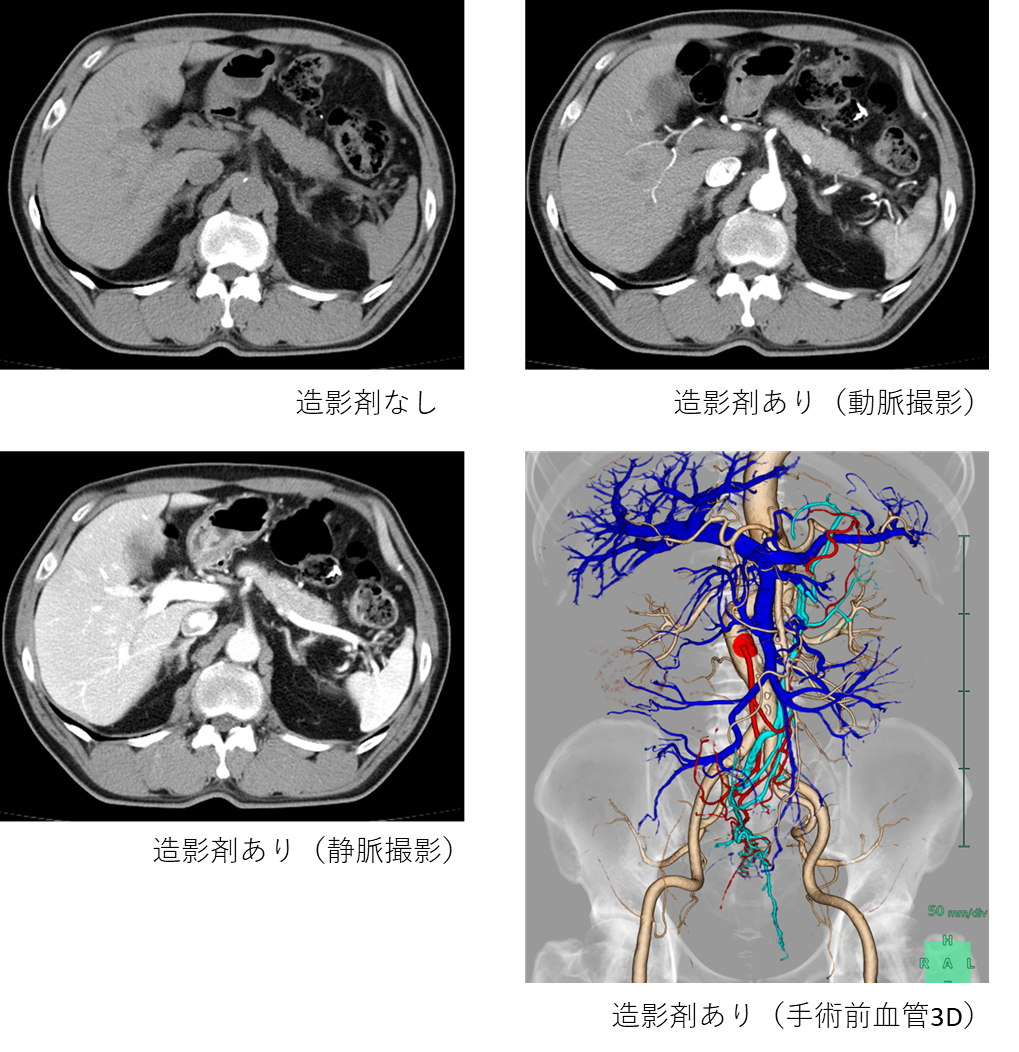

CT画像は器や血管・病気の境界はわかりにくいため様々な工夫がされており、その1つが造影剤を使用することです。

造影剤を血管から投与することで、臓器や血管にコントラストがつき病気が見つけやすくります。そのためスクリーニング検査や手術前など、多くの場面で使用されています。

また造影剤を使用した画像データから腹部・心臓3D血管画像等の作成が可能となります。